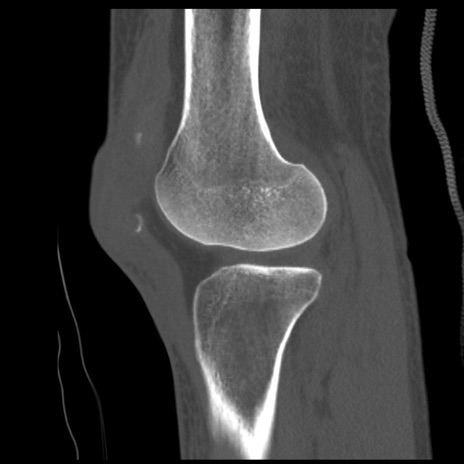

症例28 右膝関節CT(矢状断像)

右膝関節CT